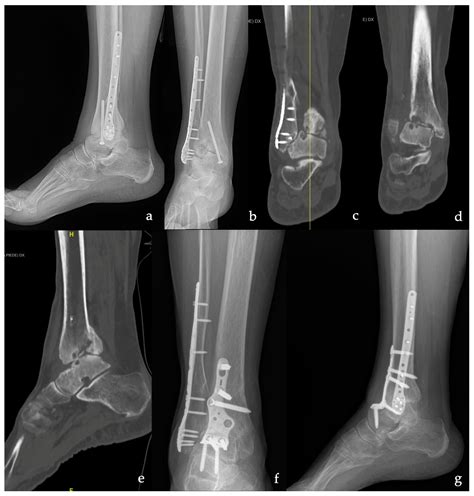

What to Expect During the Procedure

When you ask your surgeon, "What is arthrodesis from a technical perspective?", they will explain that the surgery involves removing the remaining cartilage from the joint surfaces. Once the raw bone is exposed, the surgeon uses internal hardware—such as metal plates, screws, rods, or pins—to hold the bones in the correct position. Sometimes, a bone graft (either from your own body, a donor, or a synthetic source) is placed between the bones to encourage them to grow together, a process known as osteointegration. Over several months, the body bridges the gap with new bone tissue, completing the fusion.